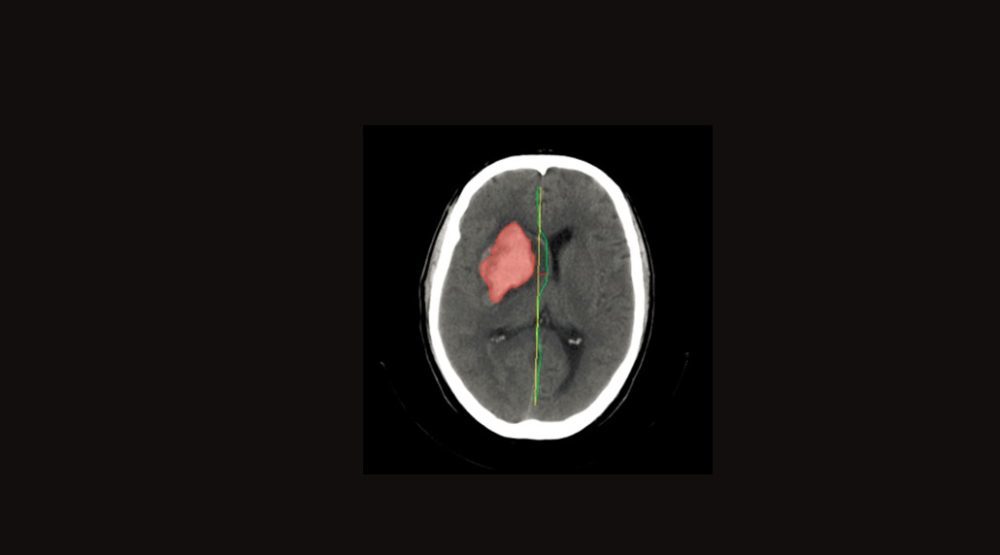

Qure.ai use cutting-edge deep learning technology to help diagnose disease and recommend personalized treatment plans from healthcare imaging data. Worldwide, the number of medical imaging procedures being performed is increasing several times faster than the number of doctors who can interpret them. Each scan is much more complex and information-rich than it used to be. Physician workload keeps increasing, as does the amount of information that they need to process before reaching a diagnosis. In this setting, the chance of human error increases, and doctors may miss a diagnosis that is evident in hindsight.

Qure’s deep learning algorithms accurately detect and highlight abnormalities, reducing the chances of missing a diagnosis. Each solution is offered as a remotely accessible API or available as a plug-in for your DICOM viewer. Qure is ideal for custom solutions or integration with a PACS system or imaging device. Qure deep learning algorithms precisely quantify disease and tumor volumes, so that patient response to therapy can be monitored closely. Applying deep learning to medical images poses a special set of challenges.

Qure.ai has tailored deep learning algorithms to deal with these challenges and to make the most of the rich 3-dimensional information contained in medical images. One of Qure’s key focus areas is algorithm interpretability, ensuring that the reason for a suggested diagnosis is clear to a doctor. As it develop new solutions and validate them in the clinical setting, Qure publish results at deep learning and medical imaging conferences. Qure believe that science progresses faster with collaborative effort, and that the best solutions are not developed in isolation. In this spirit, it is creates open-source of research.